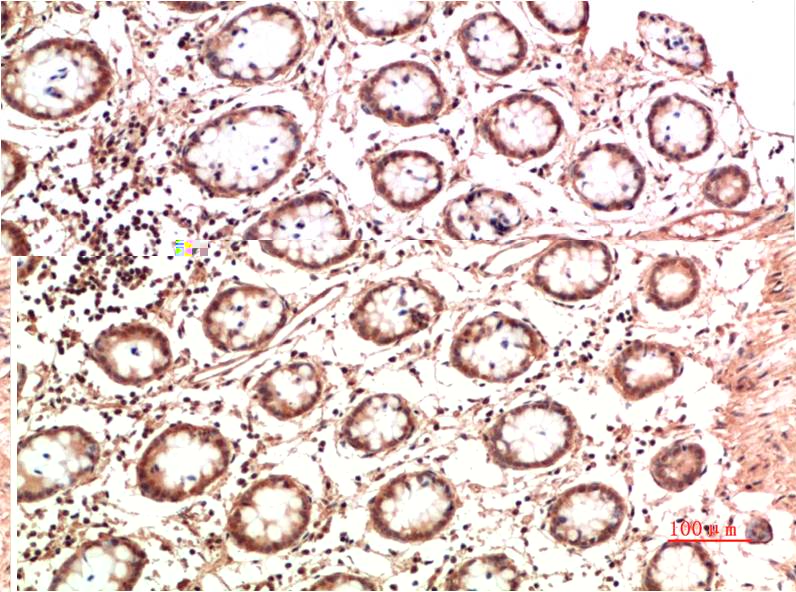

TTR Mouse Monoclonal Antibody(5G9)

Catalog NO.:BE3687

Applications :WB, IHC

Reactivity :H

| Recommended dilutions: | WB 1:1,000-2,000 IHC 1:100-200 |

| Specificity: | The TTR Mouse Monoclonal Antibody can detects endogenous TTR proteins. |